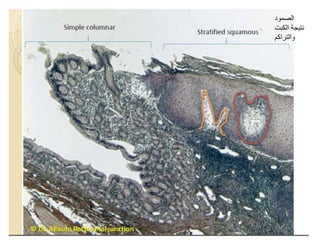

The document summarizes key aspects of liver and gallbladder anatomy and histology. It notes that hepatocytes in the liver have abundant mitochondria and are surrounded by peri-sinusoidal spaces filled with microvilli. The gallbladder stores and concentrates bile produced by the liver through absorption and secretion. The gallbladder can become inflamed or damaged due to blockage and accumulation over time.